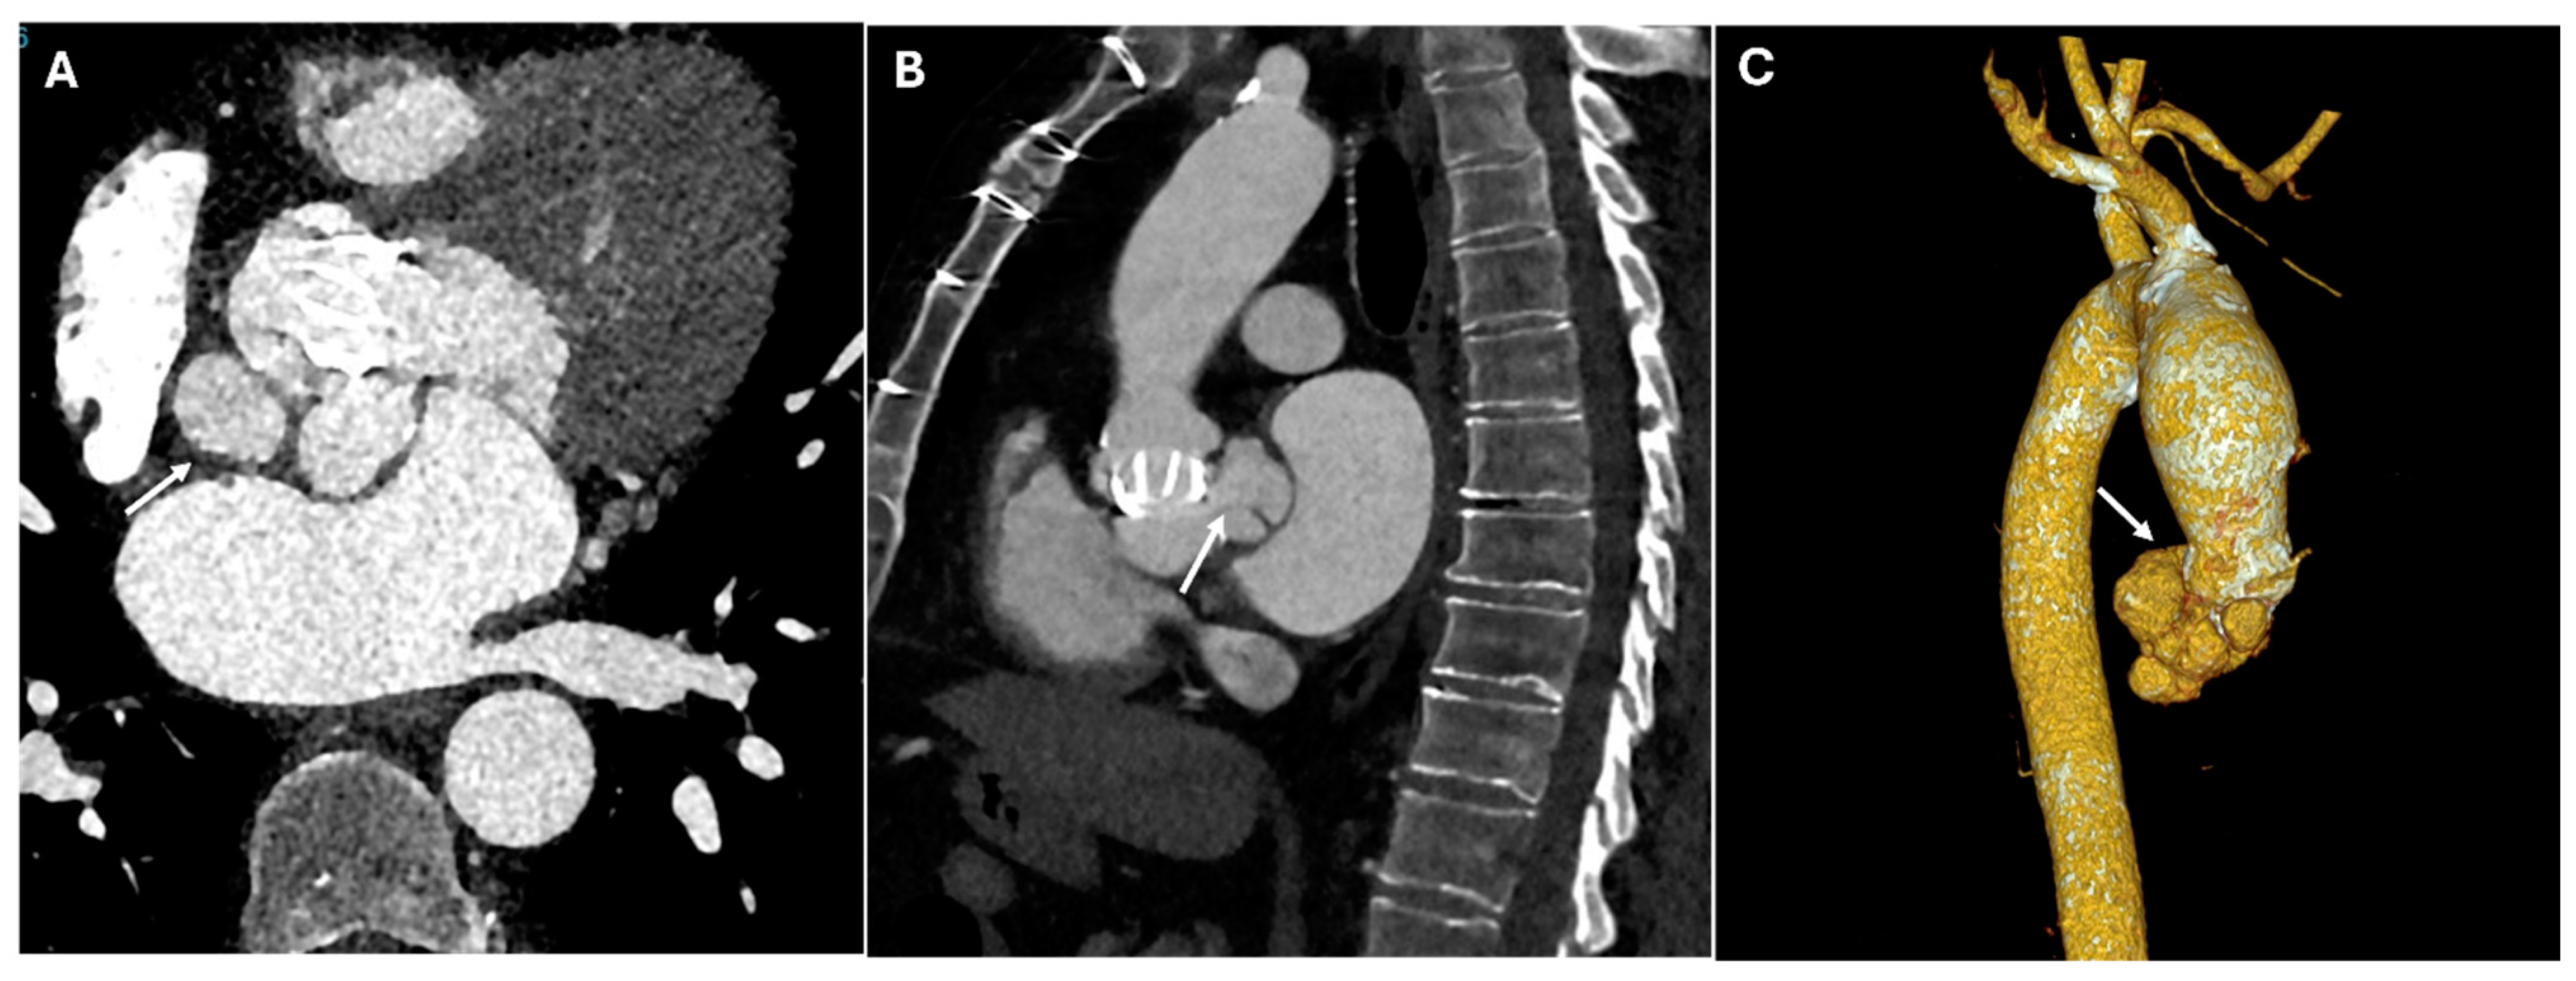

| Elephant Trunk Technique | Staged repair of extensive aortic disease | Open arch graft extending into descending aorta | Floating tubular graft within descending aorta |

| Frozen Elephant Trunk | Single-stage aortic arch + descending repair | Endovascular stent incorporated within open graft | Seamless transition between proximal graft and distal stent |

| TEVAR | Descending aortic aneurysms, dissections | Endovascular stent placement | High-density metallic structure conforming to aortic lumen |

| Endoleaks (TEVAR) | Incomplete sealing, graft migration | Persistent contrast enhancement outside stent graft lumen | Can lead to aneurysm expansion and rupture |

| Graft Migration (TEVAR) | Insufficient landing zone, poor fixation | Displacement > 10 mm on sequential imaging | May cause endoleaks or malperfusion |